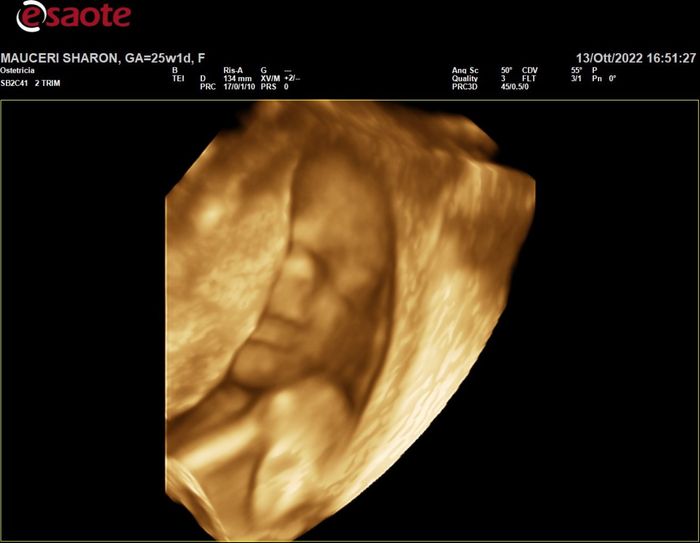

Da Sharon , Il 13 Ottobre 2022 alle 18:05

Ciao future mamme π₯° creo questo post x tutte le ragazze con DPP a gennaio 2023 (visto che ancora non l'ha creato nessuno) πIo ho la scadenza proprio il 31 dicembre 2022,...